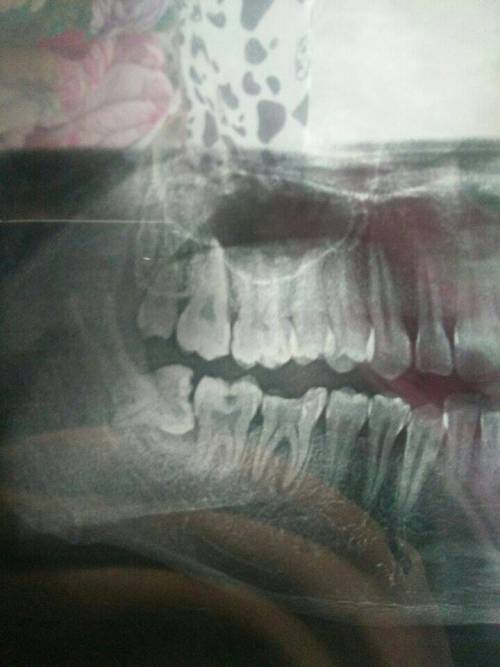

1、術前檢查:拔智齒前需要進行口腔檢查、X光片等檢查,以了解智齒的位置和周圍結構,這些檢查費用也是拔智齒總費用的一部分。

2、手術復雜性:拔智齒手術的復雜性也會影響費用,如果智齒生長位置正常,手術相對簡單;如果智齒被埋在骨頭里,需要切開牙齦和骨頭,手術難度增大,費用相應增加。